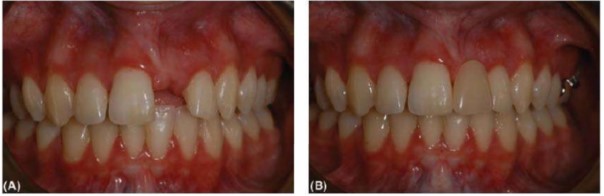

(A) Bệnh nhân này có răng 11 là phục hình trên implant không bộc lộ nướu khi cười. (B) Hình ảnh trong miệng của răng 11. Chú ý các răng cửa bên cạnh có tụt nướu nhẹ ở mặt ngoài và mặt gần trước khi điều trị. Sự mất bám dính ở mặt gần ảnh hưởng chiều cao gai nướu và rất khó hoặc không thể tái tạo lại. (C) Cũng bệnh nhân này trước khi điều trị implant, xác định vị trí của viền nướu trên răng thật. Hàm giả tháo lắp một răng đơn giản (a simple gum-fitted spoon denture) tạo thẩm mỹ chấp nhận được nhưng chức năng kém. Nó rất hữu ích cho chẩn đoán.